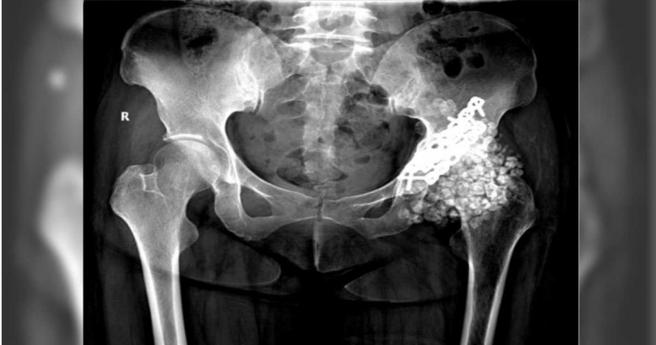

後來王女在福建醫科大學附屬協和醫院進行X光檢查,醫師透過影像發現,她的髖關節裡,竟有近300顆密密麻麻、大小不一的滑膜軟骨瘤,最大直徑為2公分,隨著髖關節活動產生劇烈摩擦,引發嚴重的骨性關節炎,其中股骨已嚴重磨損,關節的間隙幾乎消失殆盡。隨著檢查結果出爐,王女也被進一步確定為罹患「髖關節滑膜軟骨瘤病(synovial chondromatosis,SC)」。

針對髖關節滑膜軟骨瘤病,陳敏表示「解決髖關節問題,除了取出石頭,還需要在『廢墟』上重建關節」。所幸王女及時就醫治療,並經手術從身體裡取出多達259顆軟骨瘤,目前她的病情穩定,已能借助輔具下床自由行走。

王女及時就醫治療,並經手術從身體裡取出多達259顆軟骨瘤。(圖/翻攝自福州晚報)